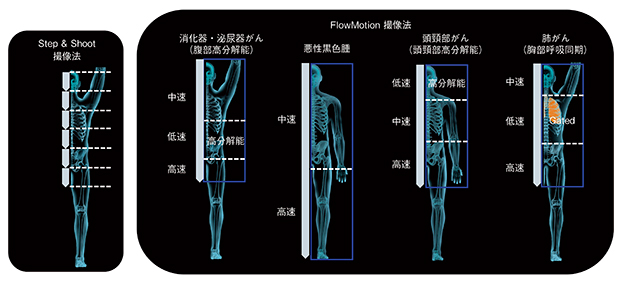

Biograph mCT Flowによって実用化された FM法は,1回の全身撮像の中で,高分解能画像が求められる臓器に対してはSNRの低下を防ぐように十分な撮像時間を確保しつつ,対象外臓器を高速撮像することによって,全体の検査時間を延長することなく撮像できる方法である。図1に,撮像範囲の設定に関し,従来法であるStep & Shoot(以下,S&S)法とFM法との違いを示す。S&S法による収集の場合,ベッドポジションの体軸方向視野を単位として撮像範囲を設定するため,臓器の大きさ,体動による影響および生理的集積の影響を加味した適切な収集条件を,臓器ごとに設定することが困難であった。同じ理由で,遅延相の撮像を行うに当たり対象臓器が十分に撮像範囲に収まらない場合,ベッドポジションを追加して撮像する必要があり,それに伴う対象外臓器への不必要なCT被ばくが避けられないという問題があった。一方,FM法では,寝台を連続移動させながらPET撮像を行い,1回の全身撮像の中で,対象臓器ごとに適切な撮像範囲と時間を設定できるため,疾患によって最適化された撮像が可能となった。また,撮像範囲がベッドポジションにかかわらず任意に設定できるため,対象外臓器へのCT被ばくを回避できるようになった。

図1 S&S法とFM法の収集条件の違い